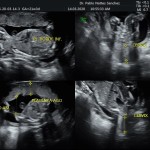

Los objetivos más importantes de esta ecografía son la evaluación de

- La vitalidad y el bienestar fetal (Doppler).

- Crecimiento fetal.

- Rastreo de alteraciones cromosómicas (sensibilidad del 60% aprox.).

- El escenario Gravídico: Placenta, liquido, Cérvix y Anexos.

- El Doppler de las arterias uterinas maternas y determinación de riesgo para pre eclampsia severa.